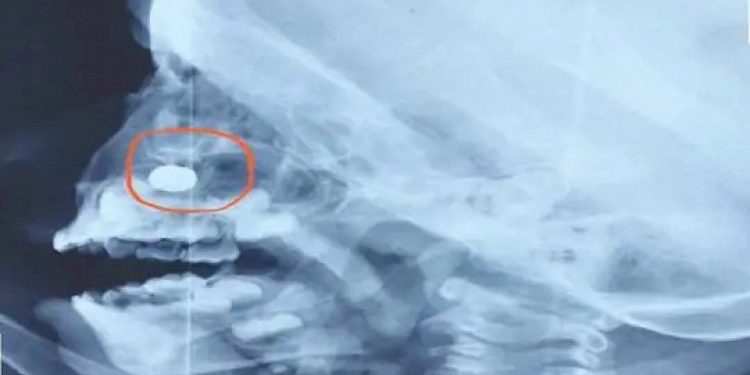

થોડા સમય પૂર્વે રાજકોટમાં એક ઘટના સામે આવી હતી જેમાં બટન સેલ બાળકને નાકમાં ફસાઈ જવાની ઘટના બાદ ગાંધીનગરમાં 3 વર્ષના બાળકના નાકમાં રાખડીમાં રહેલ LED લાઈટનો સેલ ફસાઈ જતા પરિવાર ચિંતામાં મુકાઈ ગયો હતો જો કે ડોકટરે સફળ સર્જરી કરી આ સેલને કાઢી લીધો છે, જાણવા મળતી વિગતો પ્રમાણે ત્રણ વર્ષના બાળકના હાથે બાંધવામા આવેલી LED રાખડીના કારણે બાળક અને તેના પરિવારજનોમાં દોડધામ મચી હતી. કોઈ કારણોસર બાળકે રમતરમતમાં LED રાખડીનો બટન સેલ તેના નાકમાં નાખી દેતા બાળક પર જટિલ સર્જરી કરવાની ફરજ પડી હતી.

બાળકના નાકમાં બટન સેલ ફસાઈ ગયો હોવાથી તેને શ્વાસ લેવામાં તકલીફ પડતી હોવાથી તે રડી રહ્યો છે. આથી પરિવારજનો તેને રાત્રિના સમયે ગાંધીનગર સિવિલ હોસ્પિટલ લઈને દોડયા હતા. જ્યાં તેનો એક્સ રે રિપોર્ટ કરાવતા નાકમાં બટન સેલ ફસાઈ ગયો હોવાનું સ્પષ્ટ થયું હતું.પરંતુ સિવિલમાં તેનું ઓપરેશન બીજા દિવસે શકય બનશે તેવો જવાબ મળતા પરિવારજનો બાળકને લઈને ગાંધીનગરની હાઈટેક હોસ્પિટલ ખાતે મોડી રાત્રે પહોંચી ગયા હતા. જ્યાં ઈએનટી સર્જન ડો. દેવી ગજ્જરે તેને તપાસીને તુરંત ઓપરેશન કરવાનો નિર્ણય લીધો હતો કેમકે બાળકના નાકમાંથી લોહી પણ વહેવા લાગ્યું હતું. અને બાળકને બેભાન કરીને મોડી રાત્રે જટિલ ઓપરેશન કરીને બટન સેલ કાઢી નવ જીવન આપ્યું હતું.